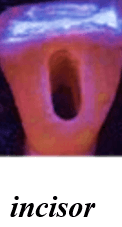

Shapes of the access cavity of all teeth

| Tooth | Access cavity shape | Average depth |

|---|---|---|

| Mandibular incisors | Triangular (placed over the lingual surface)

|

3-4 mm |

ROOT CANALS

| Tooth type | Common number of roots & canals | Variations |

|---|---|---|

| Mandibular central incisor (1) | 1 root 1 canal |

Not common: 2 canals (labial + lingual) |

| Mandibular lateral incisor (2) | 1 root 1 canal |

Not common: 2 canals common |